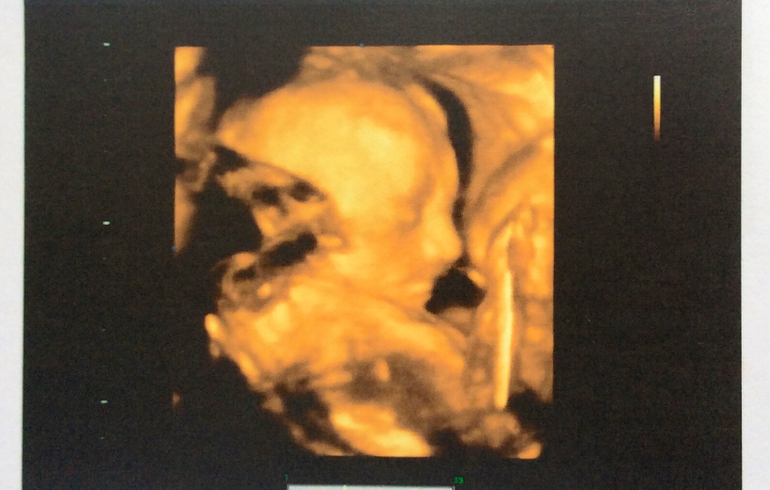

Ну а дальше, можно сказать, первые фото нашей принцессы:

Малышка очень похожа на своего папу! Я когда увидела на мониторе, просто обалдела, как будто детскую фотку мужа показали) лежит головкой вниз, также как и Тёма в позе "боксера" (ручки сжаты в кулачки у лица, в течение узи иногда закидывала их за голову). Удачное я выбрала время для узи, малышка и не спала крепко и не особо бодрствовала, а как сказала врач, отдыхала и дремала. Обвития нет, количество вод нормальное, степень зрелости плаценты соответствует сроку, ЧСС 153 уд/мин, вес уже 598 гр, длина 29 см (на 20 гр и на 1 см уже больше Тёмы). Это меня немного испугало, т.к. Тёма родился крупный 4140 гр и 57 см. Но пока рано делать выводы, посмотрим еще по последнему узи. Зато головка меньше, чем у Тёмы)) Все остальные показатели в норме и соответствуют сроку.